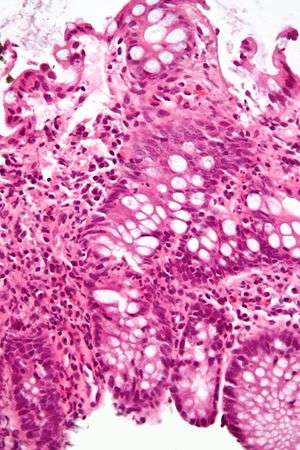

Micrograph of the small intestine mucosa showing the intestinal glands - bottom 1/3 of image. H&E stain. | |

In histology, an intestinal gland (also crypt of Lieberkühn and intestinal crypt) is a gland found in the intestinal epithelium lining of the small intestine and large intestine (colon). The glands and intestinal villi are covered by epithelium which contains multiple types of cells: enterocytes (absorbing water and electrolytes), goblet cells (secreting mucus), enteroendocrine cells (secreting hormones), cup cells, tuft cells and, at the base of the gland, Paneth cells (secreting anti-microbial peptides) and stem cells. These cells are not all present in the colon.

Intestinal glands are found in the epithelia of the small intestine, namely the duodenum, jejunum and ileum and in the large intestine (colon) where they are sometimes called colonic crypts. Intestinal glands of the small intestine contain a base of replicating stem cells, Paneth cells of the innate immune system, and goblet cells, which produce mucus.[1] In the colon, crypts do not have Paneth cells.[2]